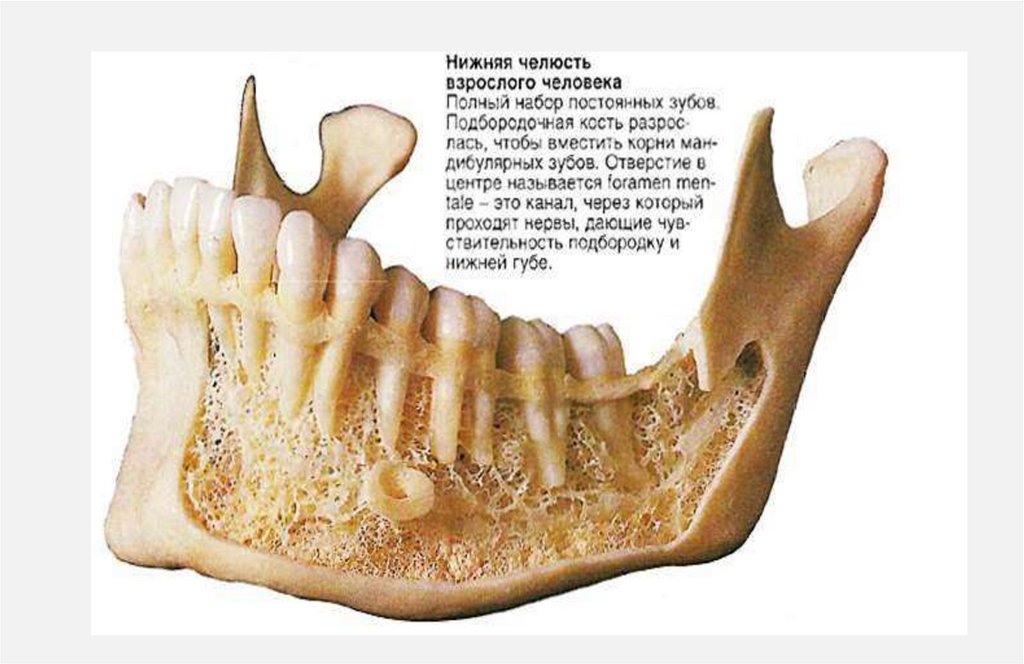

4. Череп(craium) ребенка

Череп

новорожденого не

имеет зубов. На

данном слайде

видим беззубые

челюсти и

наличие

родничков

5.

Но внутри

челюстей уже

располагаются

зачатки зубов.